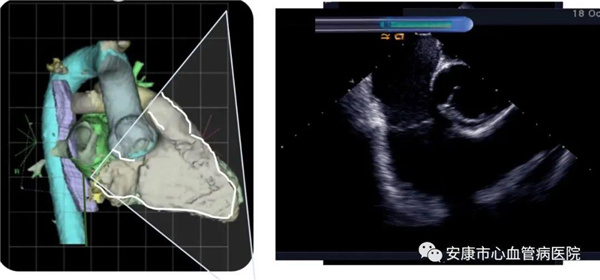

心律失常團隊在11月6日為患者在ICE引導(dǎo)下行房撲射頻消融術(shù)。穿刺左鎖骨下靜脈,導(dǎo)絲走行證實了合并永存左上腔靜脈。穿刺右股靜脈,分別送入心腔內(nèi)超聲導(dǎo)管和消融電極,超聲下建立右心室、右心房、左心室、左心房、二尖瓣和三尖瓣及三尖瓣峽部模型。ICE就像術(shù)者多了一雙天眼,可以對心臟內(nèi)部結(jié)構(gòu)一目了然,360度無死角觀察心臟結(jié)構(gòu),可以做到“所視即所及”。建模后,消融三尖部峽部,房撲很快終止,轉(zhuǎn)為竇性心律,手術(shù)獲得成功!手術(shù)用時僅70分鐘,術(shù)后病情穩(wěn)定,安全返回病房。

心腔內(nèi)超聲(Intracardiac Echocaiography ICE)是將微型的換能器安裝在心導(dǎo)管的尖端,再經(jīng)外周血管(動脈或靜脈)送至心腔,換能器發(fā)射聲波,然后將接受到的回波經(jīng)計算機處理后形成超聲圖像。由于換能器放置在心腔內(nèi),不受空氣等因素的干擾,因此比經(jīng)食道超聲檢查圖像更加清晰,可以辨別心內(nèi)的細(xì)微結(jié)構(gòu),臨床上主要用于指導(dǎo)心律失常的射頻消融治療。